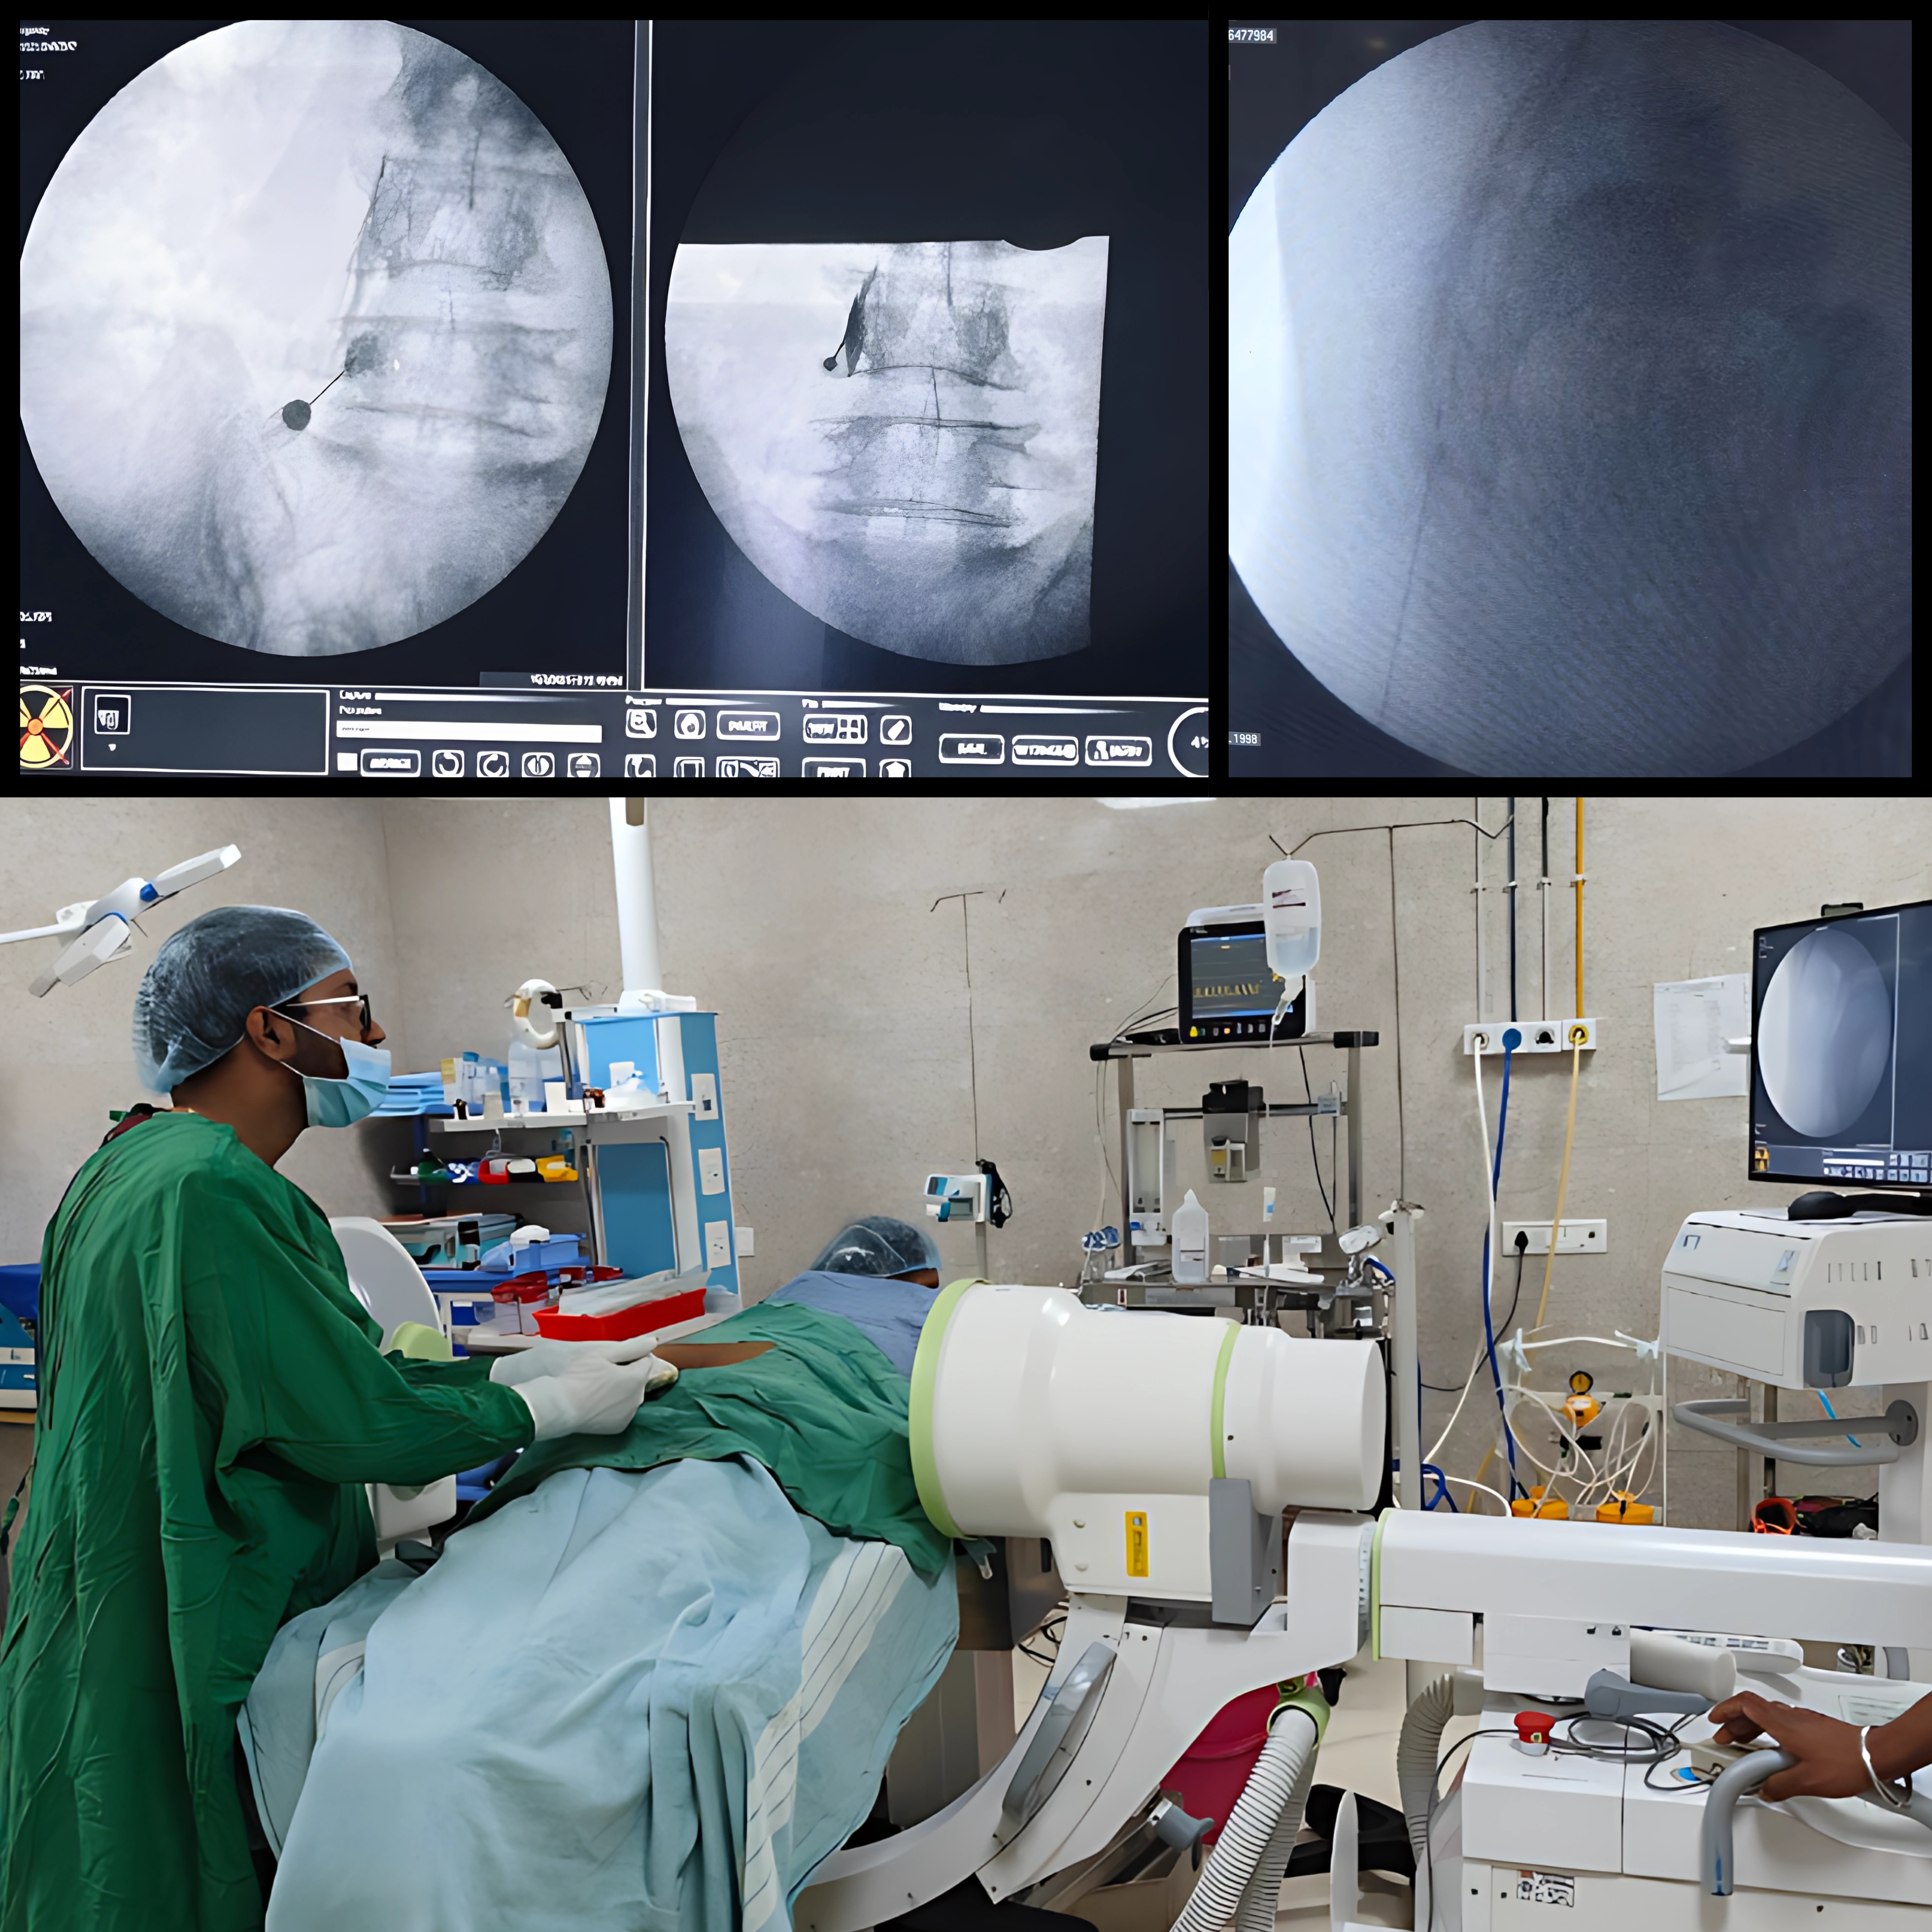

Professional Orthopedic Care for Bones, Joints and Spine

Supporting healthy bones, joints and spine with care that reduces pain and improves everyday movement, helping individuals stay active and mobile.